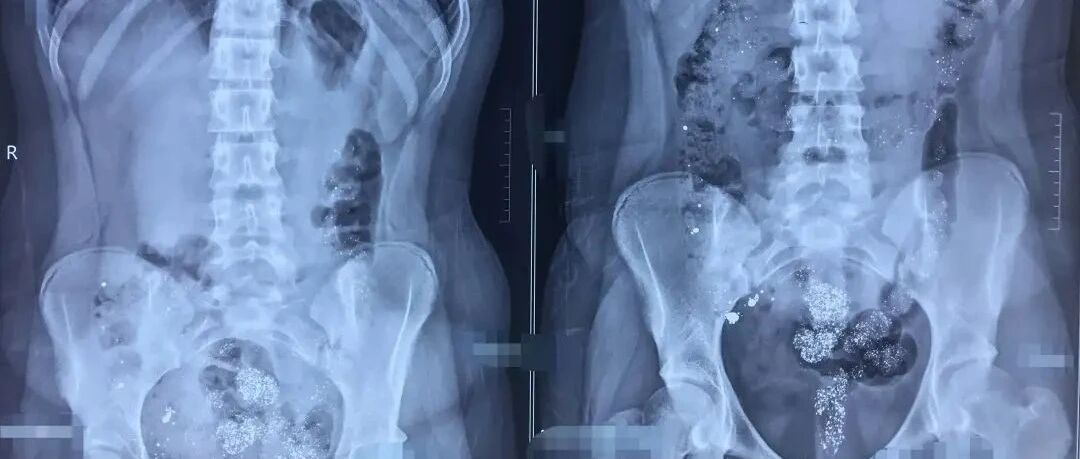

具体到安康兴安医院这个案例,从披露出来的可靠信息,一个未成年的17岁的少女看生殖系统疾病,首先不是贯彻生物医学的诊疗原则,而是先要履行社会医学和心理医学的原则。譬如,给这个女孩做生殖道侵入性检查,那这个少女是否要涉及到性生理与性心理?可能女孩出于隐私保护不愿意让家长知悉就诊?对于未成年女孩的隐私保护如何做?如何对待家长监护权的使用。还有少女所诊疗的是基本医疗范畴的疾病,民营医院的经营方向上如何来对待此类的经营,能不能把基本医疗当“生意”来做,能否把基本医疗目标的就诊者当顾客来对待?这一系列的问题都不是医疗管理的专业性问题,而是医院职业化管理问题,涉及到医院运营管理者、临床医生、手术医务人员、医务社会工作者和心理工作者等等医务职业。